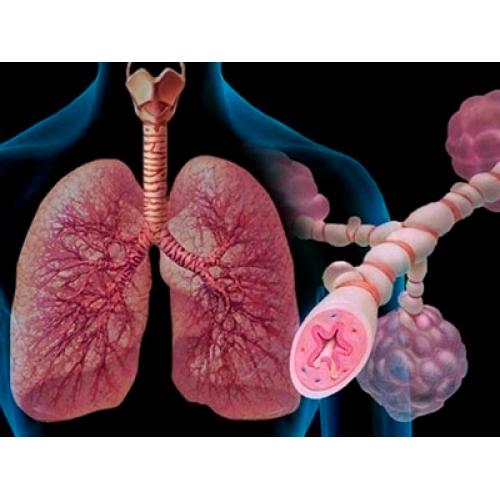

Фотографии заболеваний бронхолегочной системы